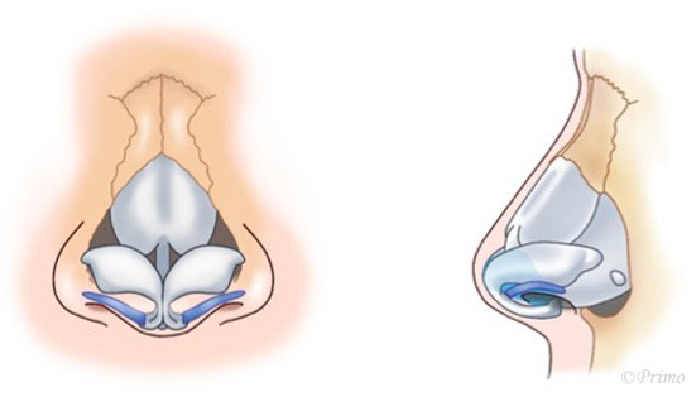

求める変化の大きさ、もともとの鼻の状態に応じ、採取部位を耳介軟骨、肋軟骨、あるいは鼻中隔軟骨から選択し、必要量のみ採取いたします。(上の図は耳介軟骨を採取して鼻中隔延長をするイメージ)

青い部分が移植した軟骨です。この軟骨の固定により、鼻の高さ、細さ、向きが大きく調節できます。